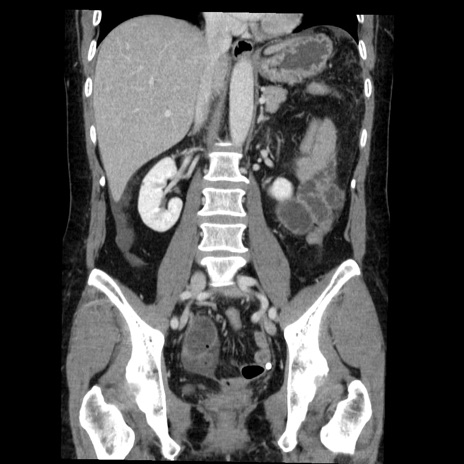

矢状断像

症例6(冠状断像)

【症例】50歳代女性

【主訴】下腹部痛

【既往歴】卵巣癌術後(8年前に当院で卵巣摘出)

【身体所見】 意識清明、腹部:平坦、腸蠕動音→、やや硬、下腹部自発痛・圧痛あり、反跳痛あり、筋性防御なし。

【データ】WBC 16000、CRP 0.01